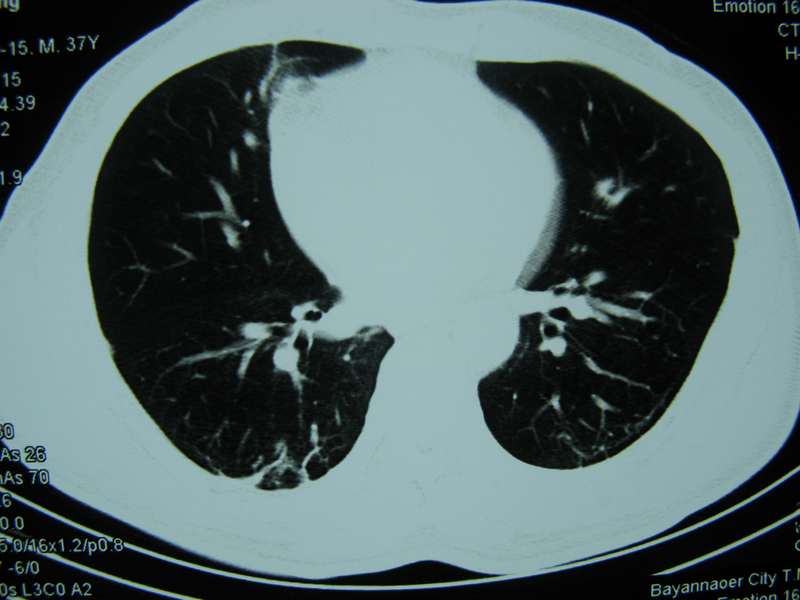

男,37岁,主述胸疼厉害,无咳嗽,无发热,血象也不高,病灶内ct值脂肪密度,右侧胸腔内少量积液,同道们考虑什么?谢谢!

两肺下叶基底段纤维灶,右肺下叶基底背侧相应胸膜肥厚,右肺中叶内侧段部分不张。前中下纵隔团块状脂肪影,随访除外胸腺脂肪瘤。